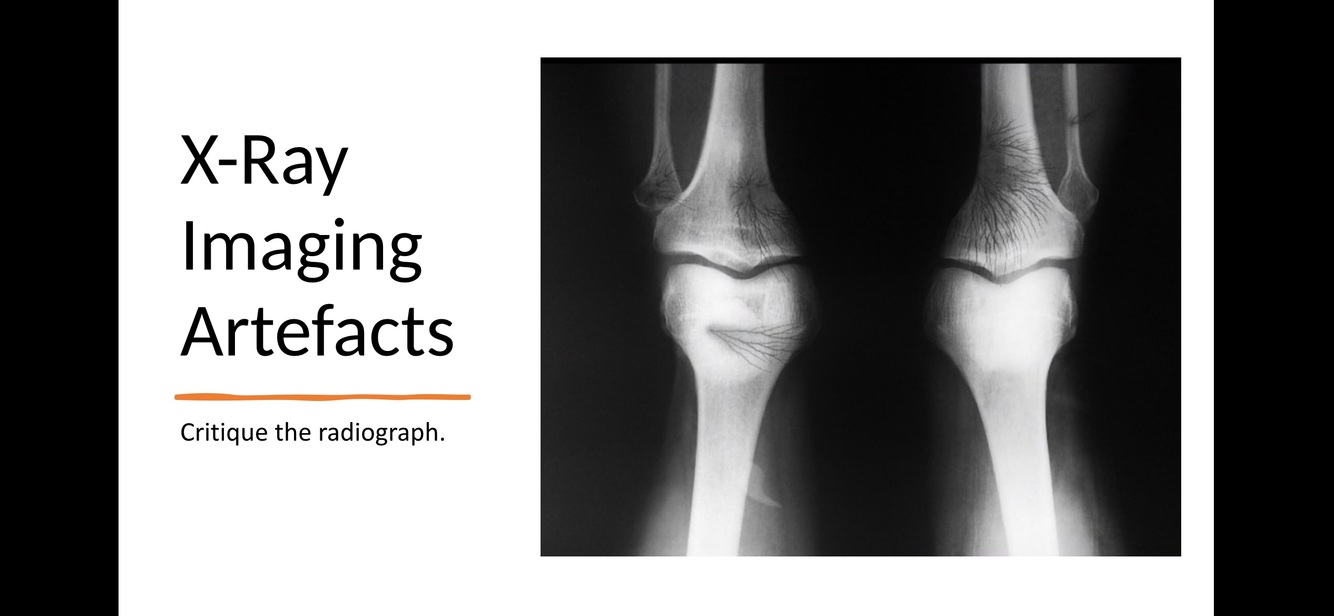

X-Ray Imaging Artefacts: Identify the artefact

Grid Line Artefact

X-Ray Imaging Artefacts: Critique the radiograph

Pony Tail

Q

Static discharge - Black “lightning” marks represent static electricity artifacts.

This occurs due to films being forcibly unwrapped or due to excessive flexing of film. (Radiopaedia)